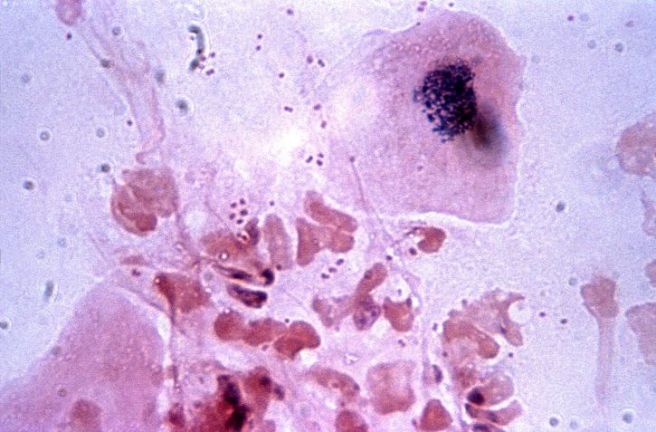

Lymphocyte는 우리 몸의 면역 체계에서 중요한 역할을 담당하는 백혈구의 한 종류로 외부에서 침입한 세균, 바이러스, 곰팡이, 이물질 등을 인식하고 제거하는 기능을 담당합니다.

혈액 검사에서 Lymphocyte 수치를 확인하는 것은 몸의 면역 상태나 감염 여부를 파악하는 데 도움이 됩니다. Lymphocyte는 T세포, B세포, NK세포로 나뉘며 각각 다른 방식으로 면역 반응을 수행합니다.

T세포는 바이러스나 세균에 감염된 세포를 직접 파괴하고, B세포는 항체를 생성하여 병원체를 제거하는 역할을 합니다. NK세포는 비정상적인 세포를 감시하고 공격하는 기능을 합니다. 따라서 Lymphocyte 수치는 단순히 높고 낮음을 기준으로 보기보다, 몸이 어떤 자극을 받았는지, 또는 면역 기능이 어떻게 반응하고 있는지를 함께 고려해야 합니다.